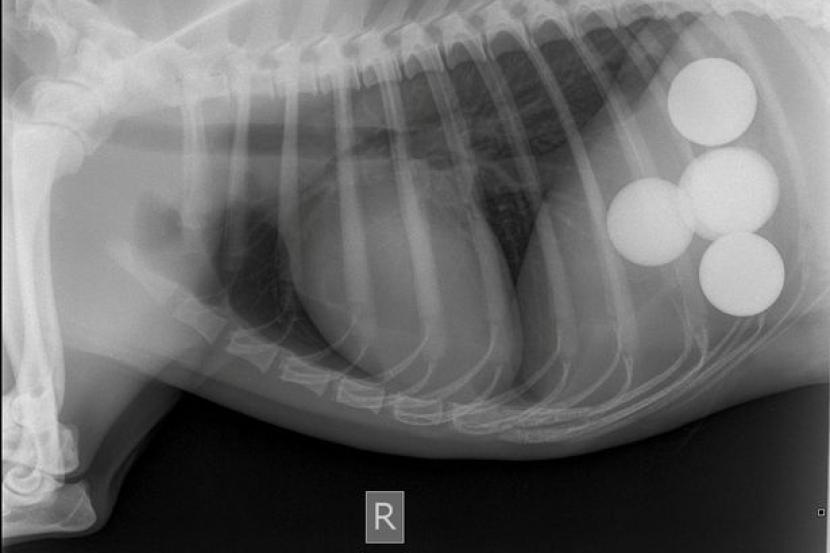

PUNCA seekor anjing yang sakit terjawab selepas imbasan sinar X di klinik haiwan mendapati terdapat lima biji bola golf di dalam perutnya.

Berdasarkan imbasan itu, dia menyedari anjingnya mengambil bola di dalam lubang apabila berjalan di padang golf dekat rumahnya.

Louis memerlukan pembedahan abdomen untuk mengeluarkan tetapi ia boleh menyebabkan kesakitan dan kecacatan.